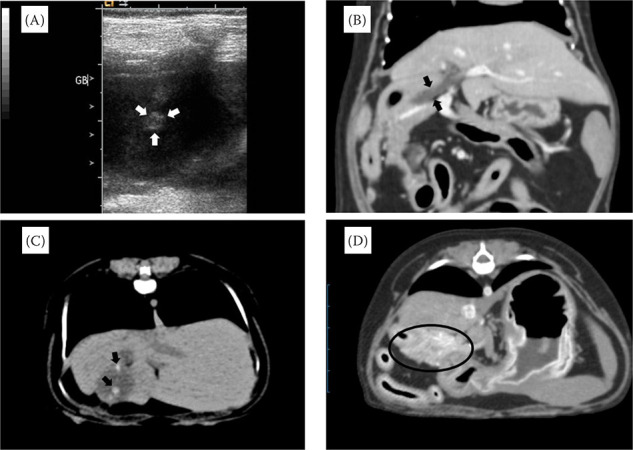

胆囊萎缩(GBA)的特征是胆囊的大小和体积缩小。在人类医学中,胆囊萎缩经常与影响胆囊和胰腺的病变同时发生,这一点已得到公认。然而,据我们所知,目前在兽医领域还很少有狗患胆囊炎的病例报道。在本研究中,我们报告了一例 7 岁约克夏梗犬患 GBA 的病例。腹部超声波检查和先进的成像技术(包括计算机断层扫描)证实了 GBA 的诊断,这些检查历时 4 年。患者最初主要表现为胃肠道症状,随后被诊断为胰腺炎并接受了治疗。与此同时,还发现了一个胆囊结节和一个疑似胆石症的异常结构。然而,在 4 年的随访中,胆囊结构消退,只剩下胆囊结节。值得注意的是,该患者没有进行胆囊切除术,除了胰腺炎相关症状外,在整个自发性萎缩过程中没有出现任何胆囊相关问题。基于这些发现,我们认为观察到的 GBA 很可能是由胆囊炎合并胰腺炎引起的。本病例强调了将 GBA 作为出现胰腺炎和胃肠道症状的犬科患者的潜在诊断的重要性。此外,它还强调了综合影像诊断在准确确定这些症状的根本原因方面的价值。

Gallbladder atrophy (GBA) is characterised by a reduction in the size and volume of the gallbladder. In human medicine, it is well-established that GBA frequently occurs together with pathologies affecting the gallbladder and pancreas. However, to the best of our knowledge, there is currently a dearth of reported cases of GBA in dogs within the veterinary field. In this study, we present a case report of GBA in a 7-year-old Yorkshire Terrier. The diagnosis of GBA was confirmed using abdominal ultrasonography and advanced imaging techniques, including computed tomography, which were performed over a 4-year period. The patient initially presented with predominantly gastrointestinal symptoms, which were subsequently diagnosed and treated as pancreatitis. Concurrently, a gallbladder nodule and an anomalous structure suspected to be cholelithiasis were identified. However, during the 4-year follow-up, the gallbladder structure regressed, leaving only the presence of the gallbladder nodule. Notably, cholecystectomy was not performed, and apart from pancreatitis-related symptoms, the patient did not show any gallbladder-related problems throughout the spontaneous atrophic process. Based on these findings, we propose that the observed GBA was likely induced by cholecystitis associated with pancreatitis. This case underscores the significance of considering GBA as a potential diagnosis in canine patients presenting with pancreatitis and gastrointestinal symptoms. Furthermore, it highlights the value of comprehensive diagnostic imaging in accurately determining the underlying cause of these symptoms.